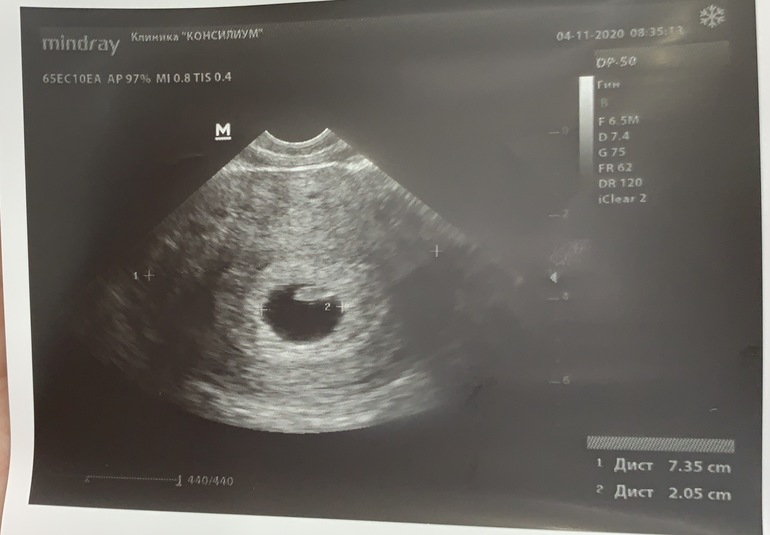

Наше первое УЗИ

Сделала узи  Погадаем?)